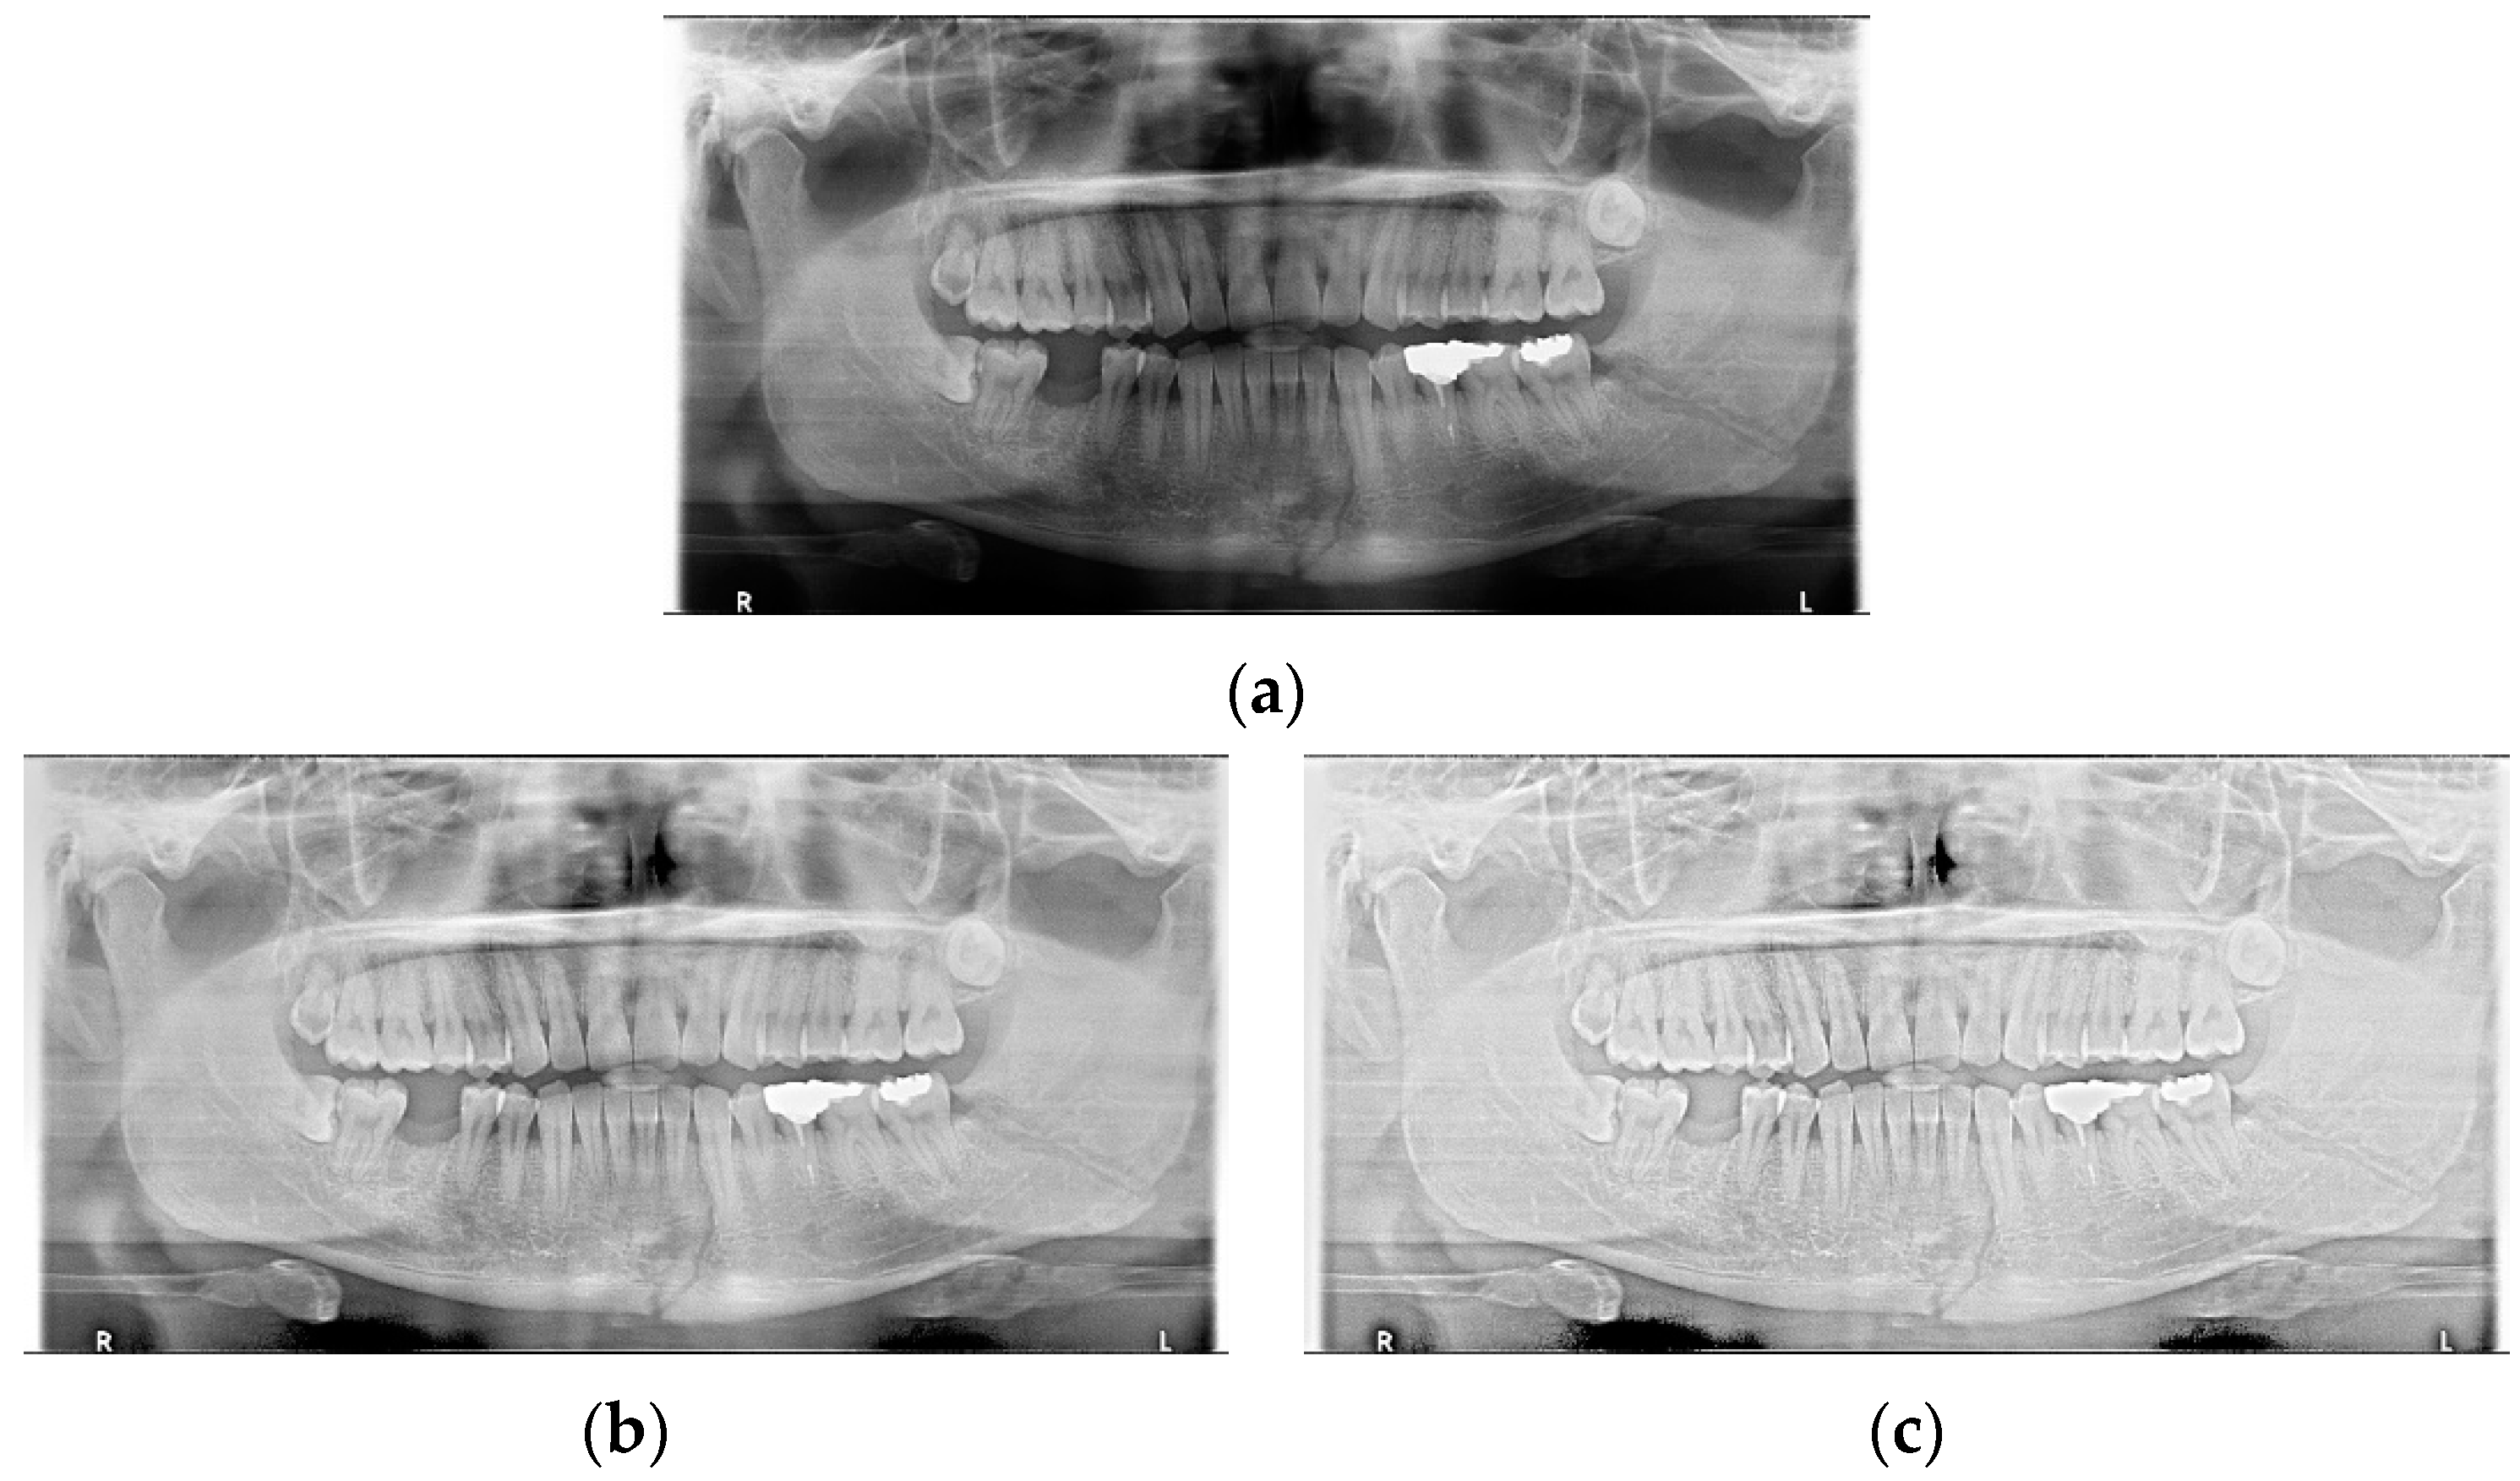

Data augmentation significantly improved the accuracy of the module during training. In the case of the LAT YOLOv4 module, the detection performance was improved by increasing the number of training data images using LAT and gamma correction, which are image pre-processing and data augmentation provided by default. LAT processes images in two ways: single-stage luminance adaptation transform (SLAT) and multiple-stage luminance adaptation transform (MLAT) []. As shown in Figure 5, SLAT strongly enhances the local details of the panoramic image; therefore, the image becomes brighter overall. Compared with SLAT, MLAT improves the visual performance of an image through tone compression of the entire image rather than local details. The LAT-processed panoramic image emphasizes the mandibular fracture better than the conventional image.

Figure 5.

The panoramic radiographs: (a) normal panoramic radiograph, (b) multiple-stage luminance adaptation transform (MLAT) panoramic radiograph, and (c) single-stage luminance adaptation transform (SLAT) panoramic radiograph.

Additionally, the YOLO-based module classified mandibular fractures into six classes (symphysis, body, angle, ramus, condyle, and coronoid process) according to anatomical location and conducted the training. Table 2 shows the comparison scores when using the standard YOLOv4 module and the module with LAT processing added. Because LAT image data augmentation can improve both misdetection and ‘undetection,’ LAT image pre-processing was used for learning mandibular fracture detection.